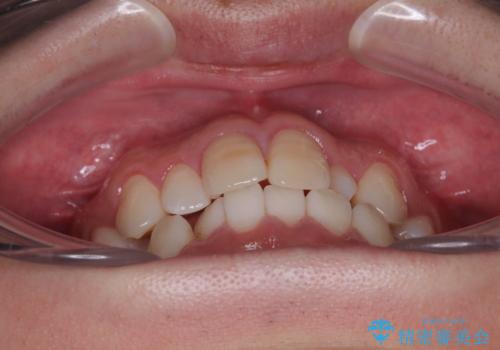

- 「上下の前歯がガタガタしているのが気になる」とのことで来院された患者様です。

上下顎前歯部に叢生(歯の重なり・ガタつき)を認め、見た目だけでなく、歯磨きのしにくさも気にされて来院されました。

インビザライン(マウスピース矯正)とワイヤー矯正のどちらが良いか悩まれていました。

そのため今回は、プラスチックブラケット+メタルワイヤーによるクリアブラケットによる治療を選択しました。